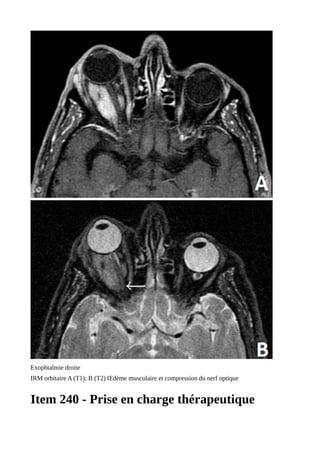

TDM ou IRM

- Exophtalmie : confirmation et

quantification par mesure de l'index oculo-

orbitaire

Exophtalmie bilatérale

Exophtalmie droite

IRM orbitaire A (T1); B (T2) Œdème musculaire et compression du nerf optique